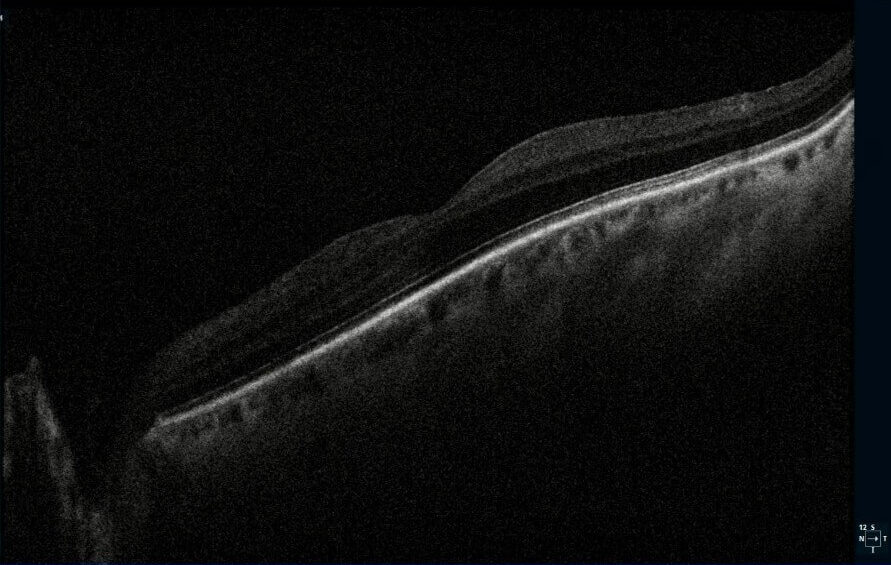

A 67-year-old male presented for a routine eye exam. The patient reported no visual complaints and denied ocular pain, photopsia, new floaters, metamorphopsia, or diplopia. His medical history included obesity and no history of systemic inflammatory or infectious disease. He denied any history of ocular trauma or surgery. The patient’s uncorrected and corrected visual acuity was 20/20 in each eye. Extraocular muscles, confrontation fields and pupils were normal. Slit-lamp examination for the right and left eye was unremarkable. Following dilation with 1% tropicamide and 2.5% phenylephrine, funduscopic examination was performed. The optic discs were normal with a cup-to-disc ratio 0.30 round. The macula in each eye was flat with normal OCT (Figure 1-2). However, examination of both eyes revealed multiple, curvilinear, pigmented chorioretinal lines originating in the posterior pole and extending outward in a distinct spiral pattern toward the midperiphery. Color fundus photographs as well as fundus autofluorescence images were obtained (Figures 3-6). There was also a punched-out chorioretinal lesion nasal to the optic nerve head in the right eye (Figure 3,5).